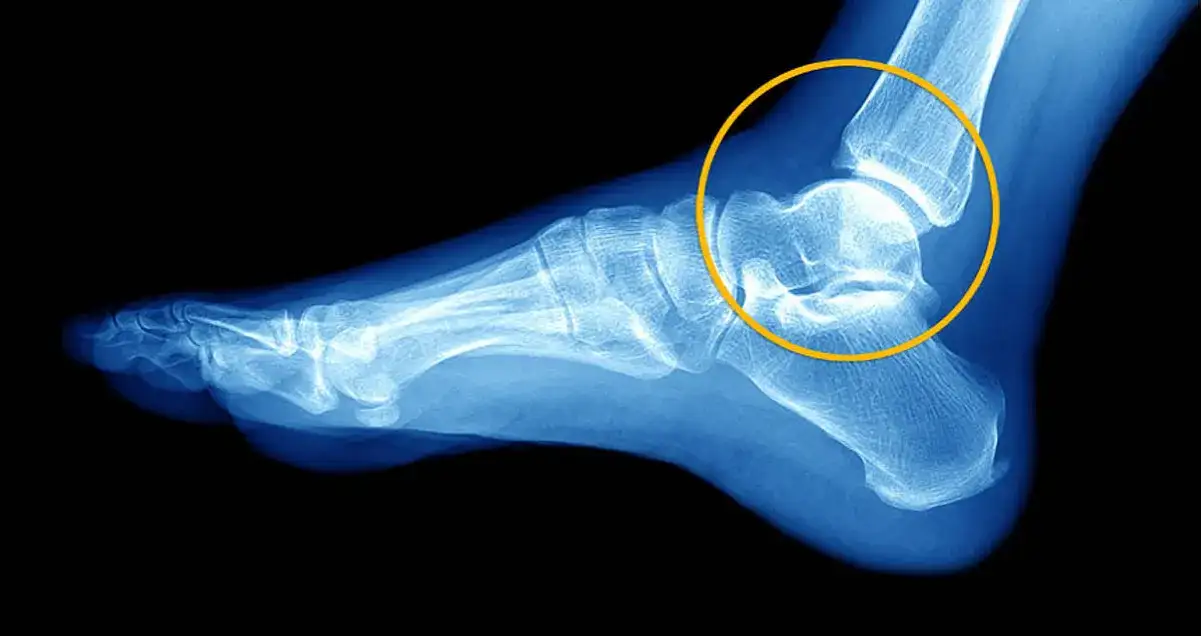

USG czy RTG? Jakie badania pomagają ocenić skalę uszkodzeń?

W celu dokładniejszej oceny skali uszkodzeń, lekarz może zlecić dodatkowe badania obrazowe. Badanie RTG (rentgenowskie) jest zazwyczaj pierwszym wyborem, gdy istnieje podejrzenie złamania kości. Pomaga ono wykluczyć uszkodzenia kostne, które często towarzyszą poważnym skręceniom. Jeśli RTG nie wykaże złamania, a objawy wskazują na uszkodzenie tkanek miękkich, często wykonuje się USG (ultrasonografię). To badanie jest niezwykle przydatne do oceny stanu więzadeł, torebki stawowej, mięśni i ścięgien, pozwalając na dokładne zlokalizowanie i określenie stopnia ich uszkodzenia. W bardziej skomplikowanych przypadkach, zwłaszcza przy podejrzeniu uszkodzeń wewnątrzstawowych, może być konieczne wykonanie rezonansu magnetycznego (MRI).